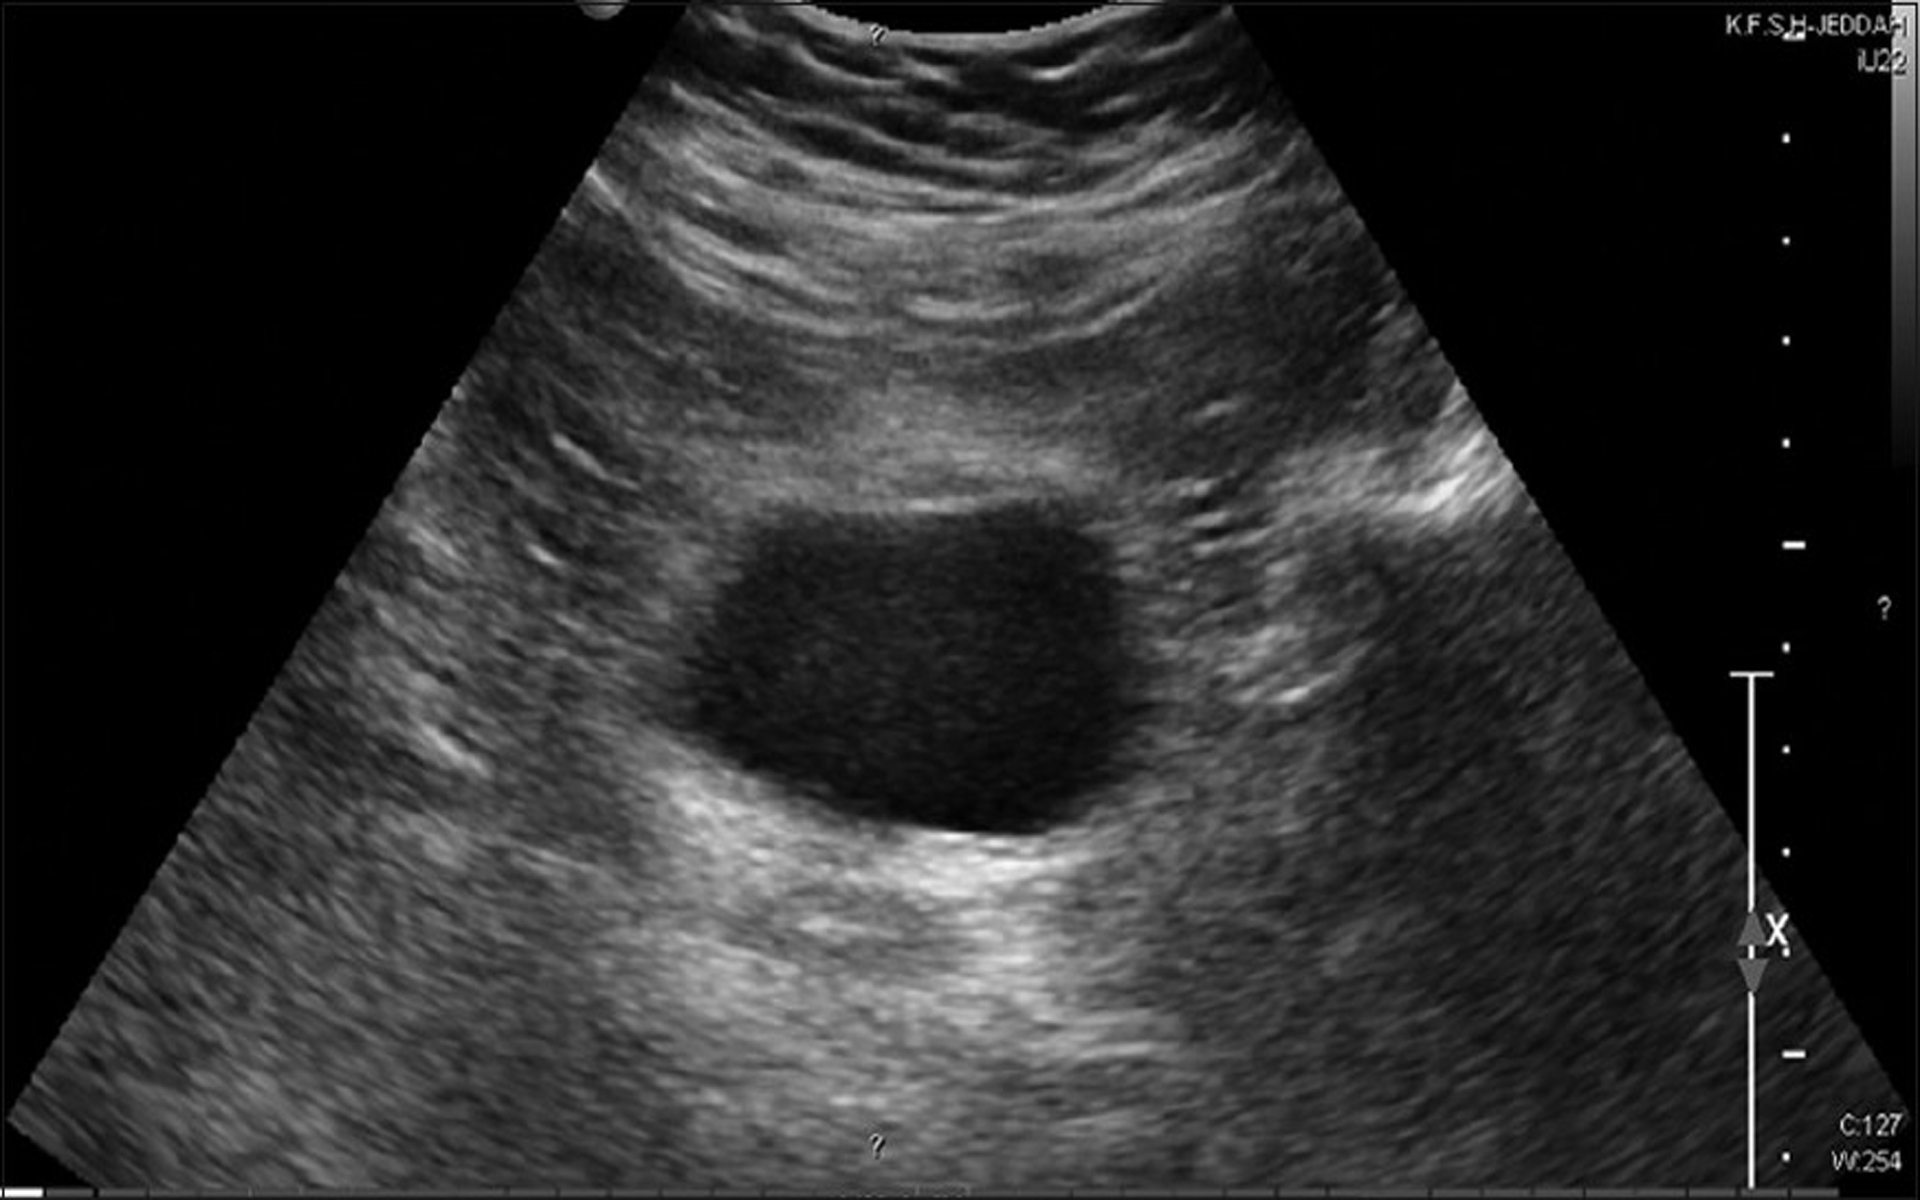

Ultrasonido Pélvico Ginecológico Dr. Emmanuel Acuña

Source: dremmanuelradiologo.mx